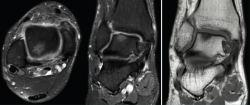

Figura 2. Imágenes de resonancia magnética (RM) en T2 (corte sagital y coronal). Imagen de la tomografía axial computarizada (TAC), corte coronal. Se observa una lesión osteocondral en la cúpula astragalina de 15 × 11 mm (diámetro anteroposterior y medial-lateral) según la RM y de 9 × 7 mm según la TAC.